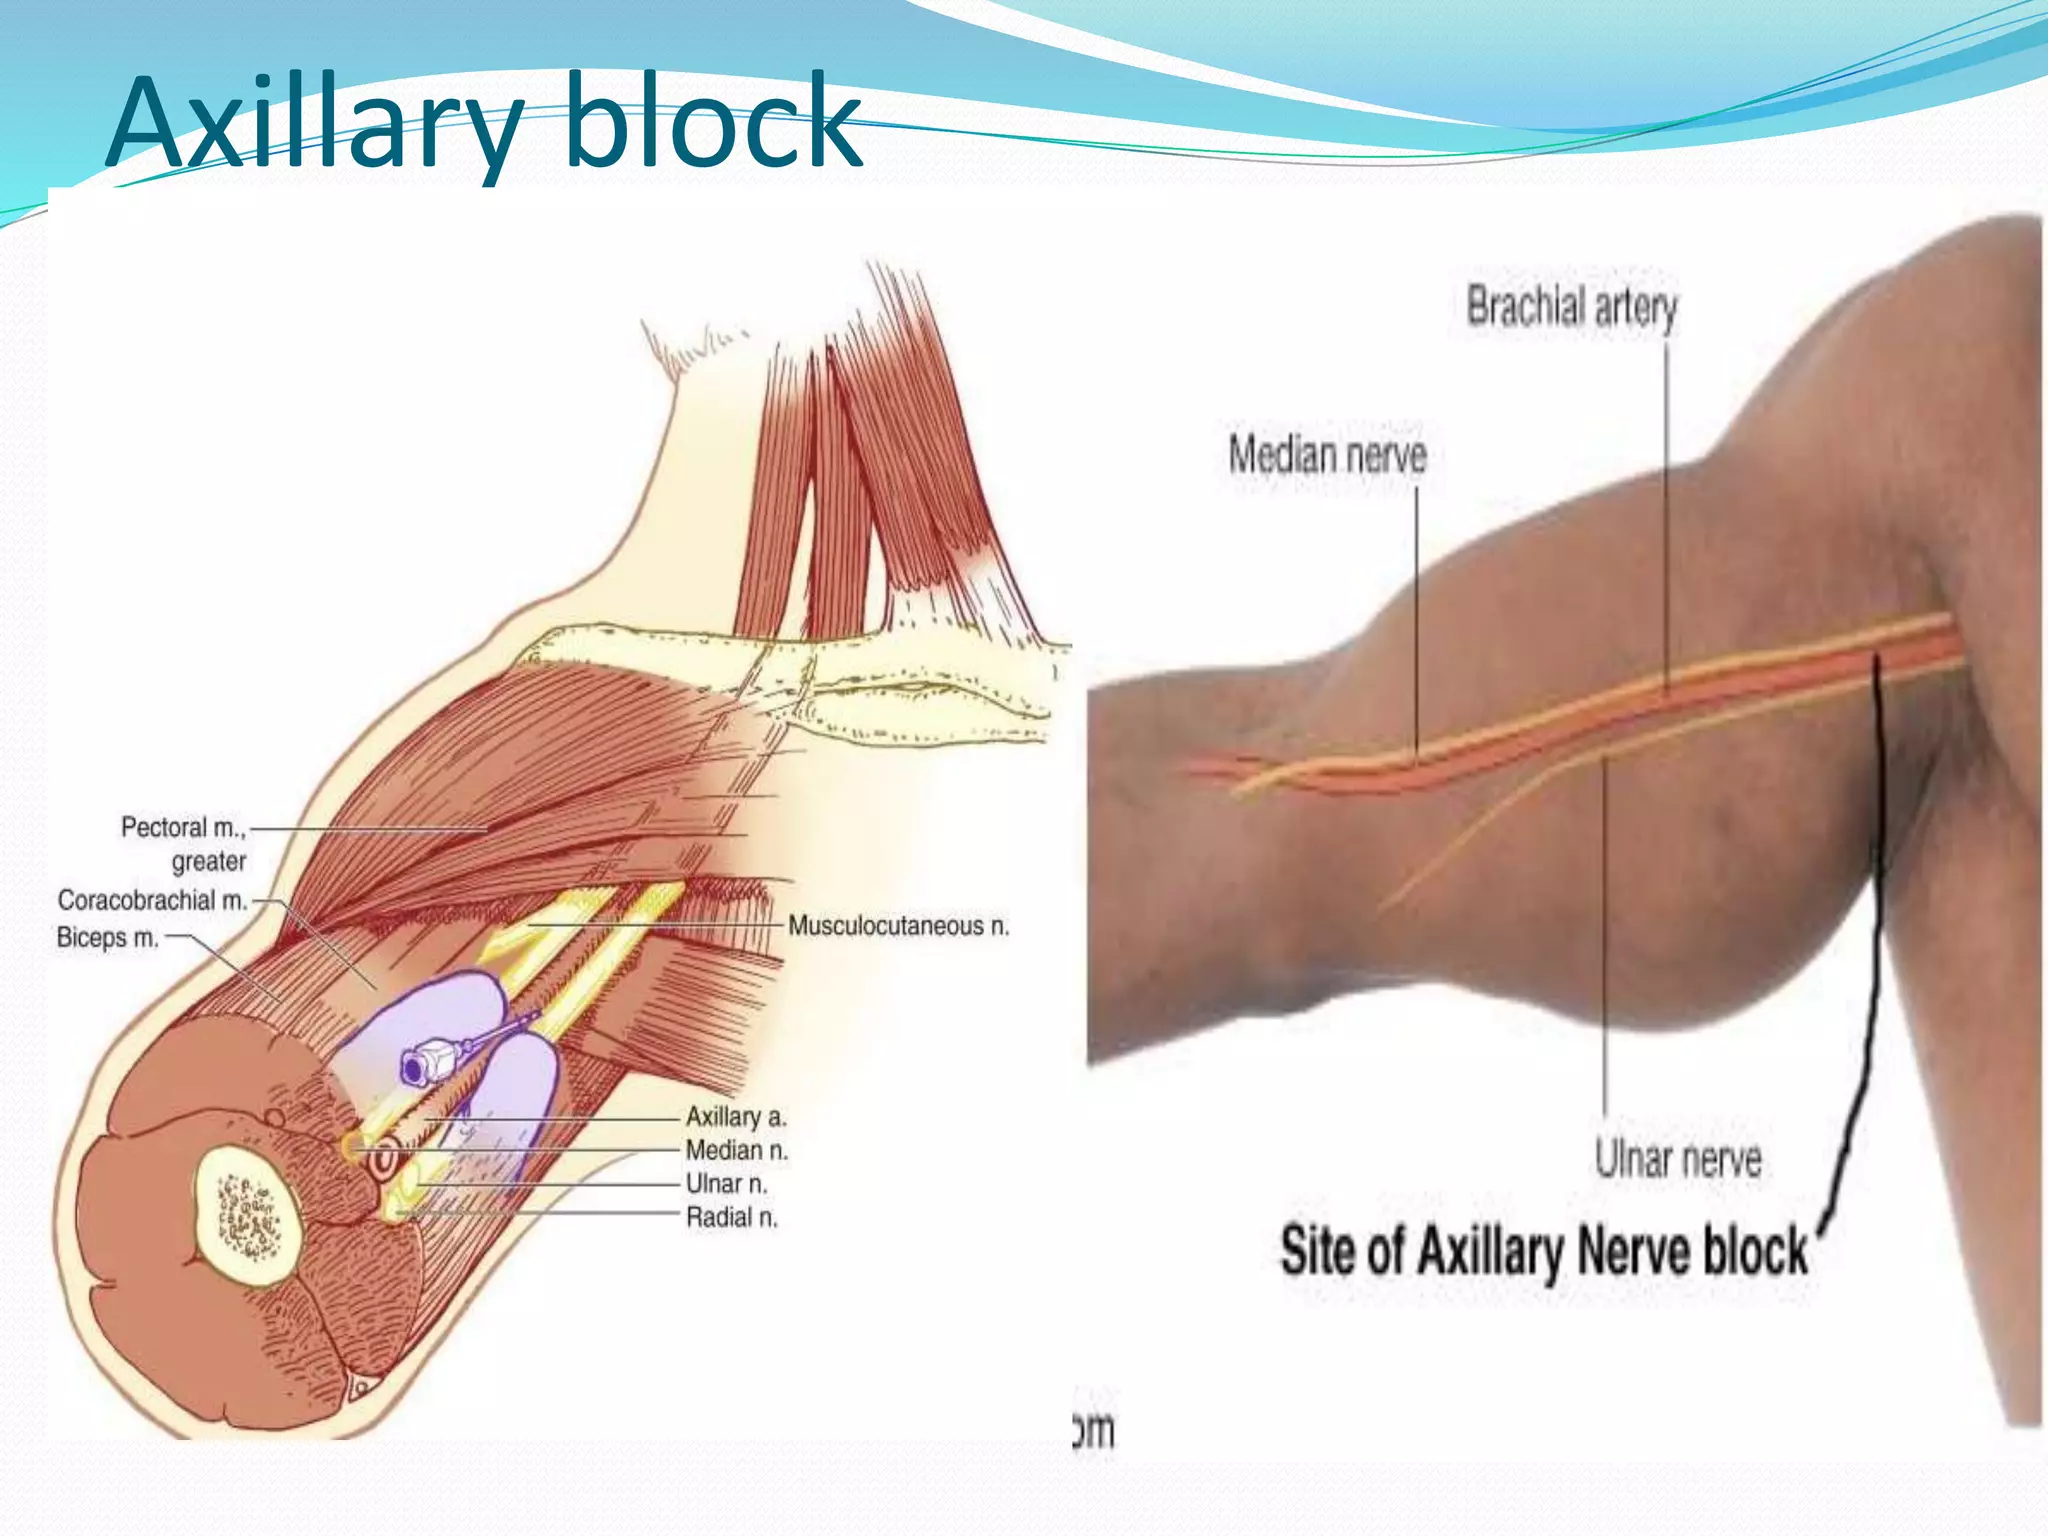

This document provides an overview of brachial plexus anatomy and techniques for brachial plexus nerve blocks. It begins with a description of the brachial plexus formation from cervical and thoracic nerve roots and its branching pattern. Four main approaches for brachial plexus nerve blocks are described: interscalene, supraclavicular, infraclavicular, and axillary. Details are provided on the anatomy and techniques for performing interscalene and supraclavicular brachial plexus blocks. Ultrasound guidance is discussed as an advancement which allows real-time visualization of needle and nerve. Complications are also summarized.